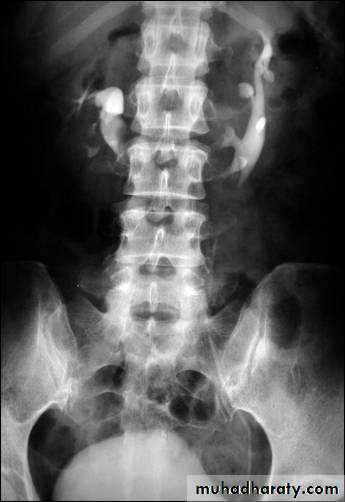

Horse shoe kidney :-*lower poles fused *low positioned kidneys *parallel to spines.*malrotated medially